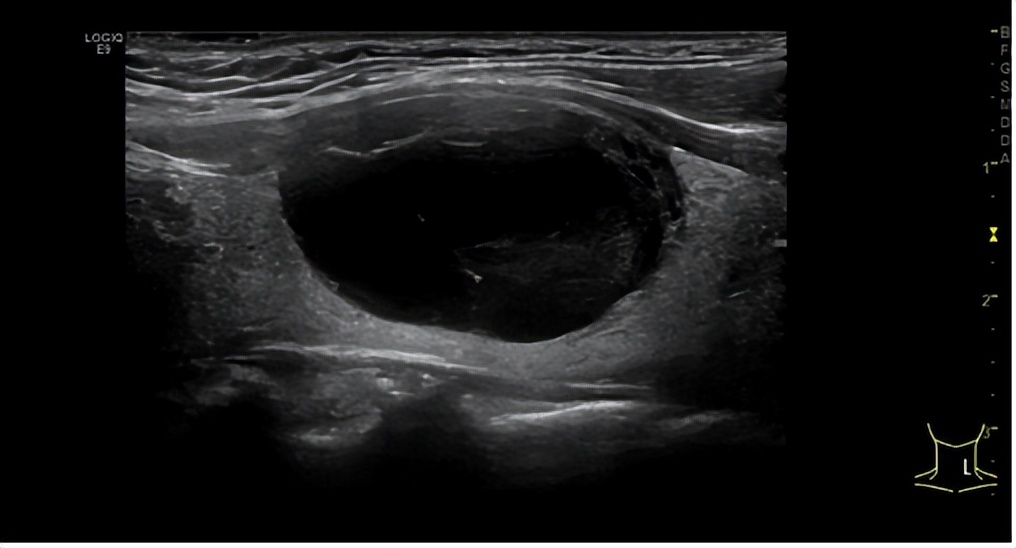

张阿姨在女儿的陪同下来到了省二医,找到超声科主任医师马力进行甲状腺超声检查,结果显示张阿姨甲状腺左侧叶有一个大小约2.9cm*1.9cm的囊实性结节,右侧叶另有两个囊实性结节,分别为1.7cm*1.2cm、0.6cm*0.5cm。

术前,张阿姨左侧叶混合性结节情况

马力主任医师当即表示,结节呈囊实性,较前检查明显增大,以后依然有增大趋势,将来可能会压迫气管、食管等,建议微创处理!经过沟通,治疗方案决定将左侧叶结节先进行抽液硬化,随后对双侧叶各个结节进行微波消融治疗。